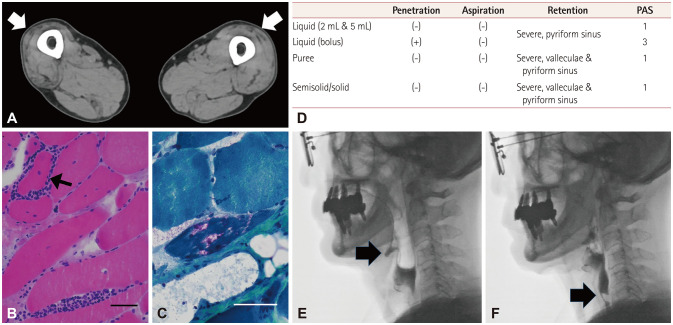

Differentiating Inclusion Body Myositis From Amyotrophic Lateral Sclerosis Based on the Features of Dysphagia: Insights From a Patient With Rapidly Progressive Dysphagia.

基于吞咽困难的特征来鉴别包涵体肌炎和肌萎缩侧索硬化症:来自一位快速进展性吞咽困难患者的见解。